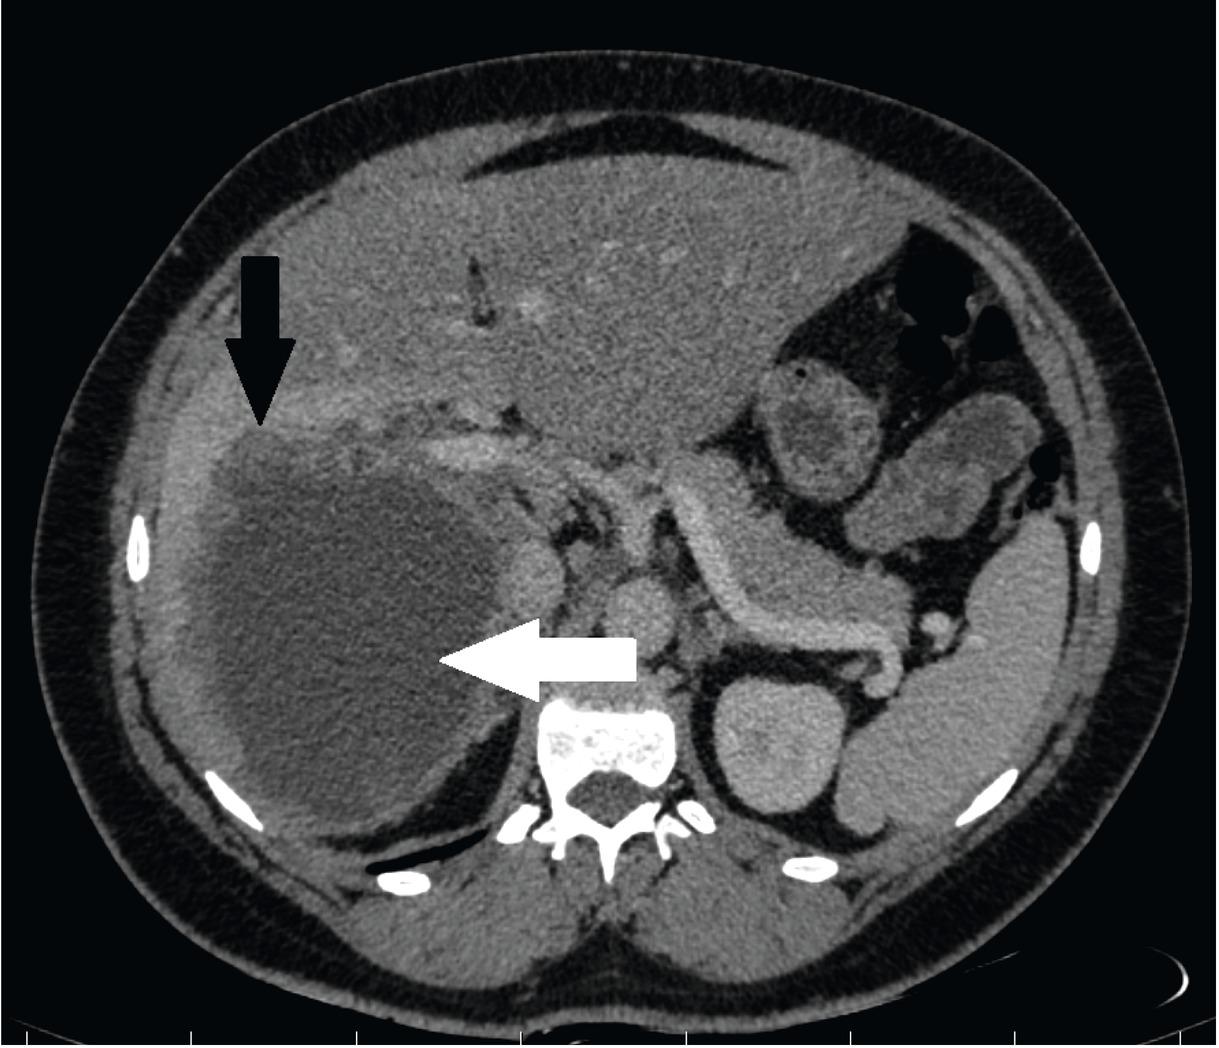

Fig. 1